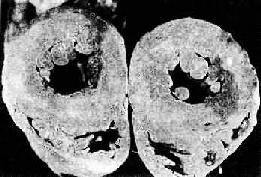

3.超聲心動圖通過測定心室容量、室壁運動和左心室射血分數等情況,有助於確立急性心肌梗死的梗死部位、梗死範圍及左、右室功能障礙程度,提供預後信息。二維超聲心動圖檢查在幾乎全部透壁性急性心肌梗死病人中均顯示區域性室壁運動異常。